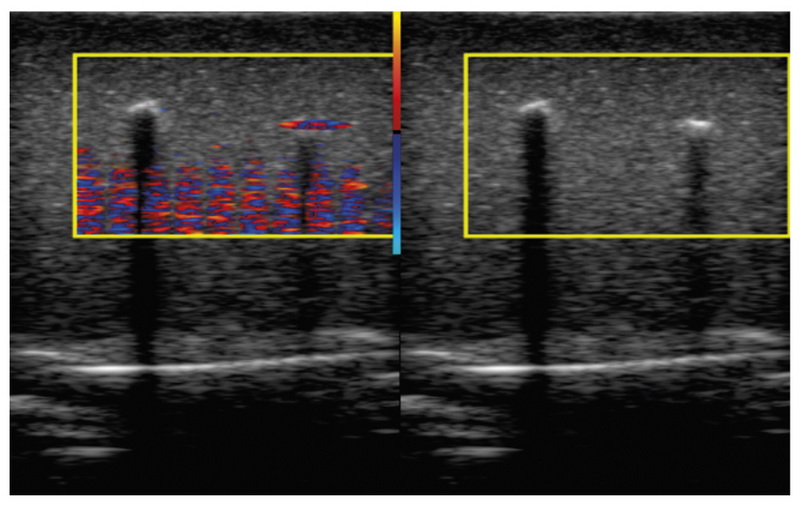

Обоснование. Мерцающий артефакт в доплеровских режимах ультразвукового исследования проявляется быстрой хаотической сменой окрашенных пикселей на экране прибора. Явление, которое можно использовать в качестве полезного диагностического признака, исследовано недостаточно. Большинство предположений о причинах артефакта сделаны на основании изображений с экрана ультразвукового прибора без глубокого изучения свойств принимаемых сигналов.

Материалы и методы. Радиочастотные ультразвуковые сигналы были записаны при исследовании фантомов. Исследовались как объекты, приводящие к появлению мерцающего артефакта на экране прибора, так и имитации сосудов и мягких тканей. Сбор данных проводился с июля 2016 по март 2021 г. Данные получены при помощи исследовательского ультразвукового прибора «Сономед-500» с датчиками 7,5 L38 и 3,4 C60.

Содержимое базы данных. Представлена база данных, содержащая радиочастотные сигналы, полученные с выхода формирователя луча из приёмного тракта ультразвукового медицинского диагностического прибора в режиме цветового доплеровского картирования и В-режиме. Представленные в базе данных сигналы содержат признаки мерцающего артефакта. База состоит из исследований пяти различных фантомов общим объёмом 10,5 ГБ. Радиочастотные данные сохранены в бинарном виде. Настройки сканирования, необходимые для анализа радиочастотных данных, содержатся в текстовых файлах. Каждое исследование сопровождается примером характерной сонограммы в графическом формате. База данных доступна по адресу: https://mosmed.ai/datasets/ultrasound_doppler_twinkling_artifact.